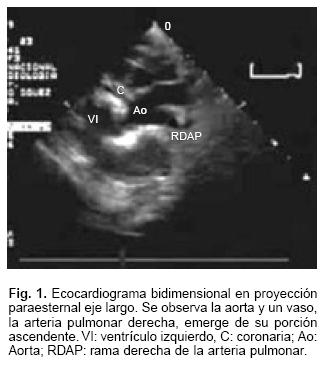

La radiografía de tórax mostró cardiomegalia grado III y flujo pulmonar aumentado. En el ecocardiograma (Fig. 1) se observó que la rama derecha de la arteria pulmonar (RDAP) nacía de la aorta ascendente. Había marcada hipertensión arterial pulmonar. Tenía mala función ventricular con fracción de eyección de 33%. El estudio hemodinámico (Figs. 2 y 3) demostró que la presión sistólica de la rama izquierda de arteria pulmonar era suprasistémica de 80 mm Hg y en la rama derecha era de 60 mm Hg, igual a la sistémica; se observó gran retardo del vaciamiento de la vena pulmonar izquierda; había un conducto arterioso permeable. La angiorresonancia magnética (Figs. 4 y 5) corroboró los diagnósticos y mediante la reconstrucción permitió ver una estenosis de la vena pulmonar superior izquierda. Por la edad de la paciente y la presencia de la obstrucción venosa pulmonar fija, se consideró candidata a cirugía.